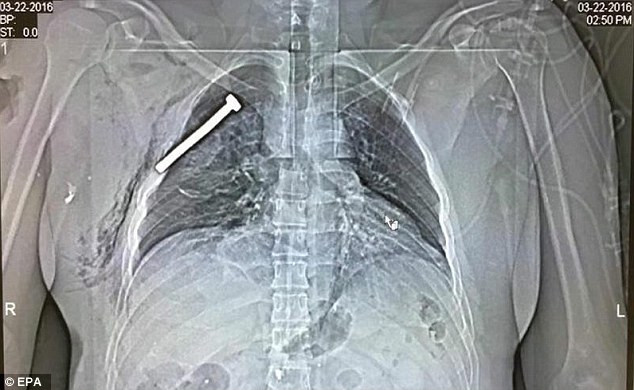

Ảnh X-quang chụp phổi của một nạn nhân sống sót sau vụ khủng bố hôm 22/3. Ảnh: EPA

Hình ảnh chụp X-quang phổi của một nạn nhân bị thương nhưng may mắn sống sót trong vụ khủng bố xảy ra tại sân bay Zaventem (thủ đô Brussels, Bỉ) hôm 22/3 vừa qua.

Sau khi vụ khủng bố xảy ra, nạn nhân này đã được đưa đến bệnh viện quân đội ở Neder-over-Heembeek, phía bắc thủ đô Brussels.

Qua hình ảnh, có thể thấy trong phổi của nạn nhân bị găm một chiếc đinh có chiều dài khoảng 3 inch (tương đương 7,6 cm). Vị trí của chiếc đinh chỉ cách trái tim của nạn nhân vài cm.

Chiếc đinh này được cho là đã bắn ra khi một quả bom đinh phát nổ tại sân bay Brussels, cùng loại với thiết bị nổ được tìm thấy khi cảnh sát lục soát một căn hộ ở quận Schaerbeek, Brussels. Ngoài ra, trong cuộc đột kích này, cảnh sát địa phương còn tìm thấy một số chai hóa chất và cờ của tổ chức Nhà nước Hồi giáo tự xưng (IS).